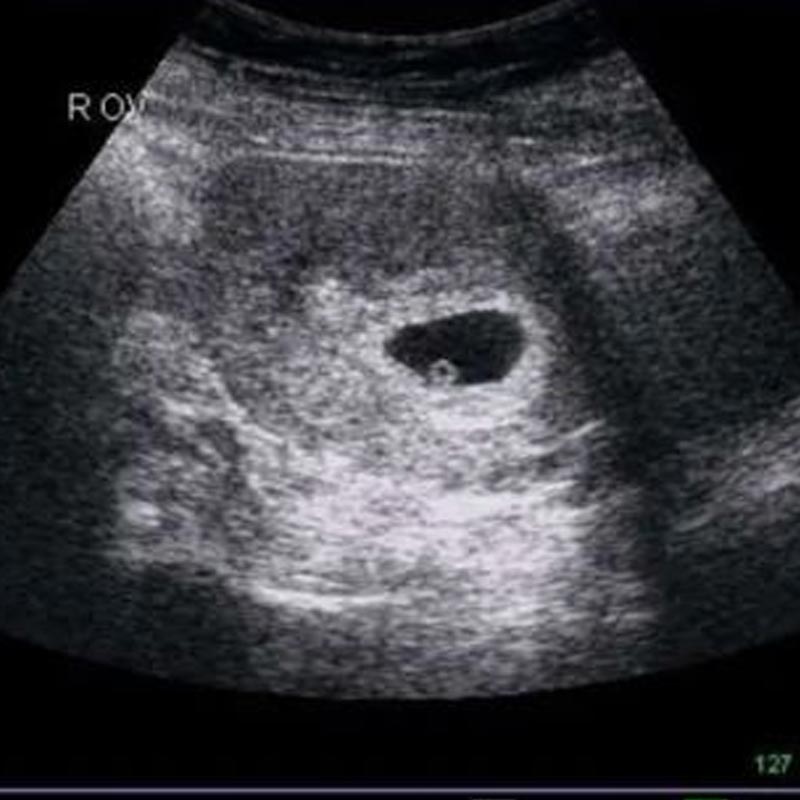

Vào tuần thai thứ 6, thai nhi thường có chiều dài khoảng 0,5 - 0,6 cm và có kích thước ước chừng như một hạt đậu nhỏ xinh. Từ góc độ y khoa, đây là giai đoạn quan trọng, khi các cấu trúc như thận, gan và phổi chuẩn bị hình thành. Hệ thần kinh của thai nhi cũng phát triển, tạo nền tảng cho việc liên kết và truyền nhận thông tin giữa các tế bào sau này. Qua siêu âm, có thể thấy rõ những nếp gấp trên khuôn mặt, phát hiện vị trí của màu mắt, mũi… Cũng có trường hợp việc siêu âm cho thấy sự đập của tim thai, giúp mẹ bầu cảm nhận rõ ràng hơn sự hiện diện và sức sống của bé.

Điều đặc biệt trong giai đoạn này là các chồi nhỏ trên ngực và lưng của thai nhi dần phát triển thành chi. Tuy nhiên, chúng còn rất nhỏ, mới chỉ là những mầm tay, mầm chân. Dr. Bích Trang BMT chia sẻ rằng lúc này, hệ tim mạch của thai nhi đã hoạt động ở mức sơ khai và một số thiết bị siêu âm hiện đại có thể phát hiện nhịp tim. Đây luôn là khoảnh khắc thú vị, khi bác sĩ cho mẹ nghe nhịp tim đầu tiên của con, giúp mẹ thêm yên tâm và gắn kết với bé từ sớm.

Theo khuyến nghị từ nhiều chuyên gia, mẹ bầu nên đến bệnh viện hoặc cơ sở y tế uy tín để khám thai định kỳ, lý tưởng nhất là theo đúng lịch hẹn của bác sĩ. Trong tuần thứ 6, một số bác sĩ có thể chỉ định thực hiện siêu âm qua ngả âm đạo để kiểm tra vị trí của thai và xác nhận tim thai. Tiếp theo, mẹ có thể được hướng dẫn làm một số xét nghiệm máu, đo nồng độ hormone hCG, hoặc xét nghiệm nước tiểu để kiểm tra sức khỏe tổng quát.